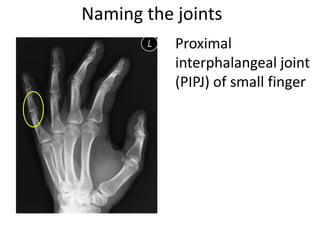

- Naming the bones, joints, tendons, nerves and skin landmarks of the hand and wrist.